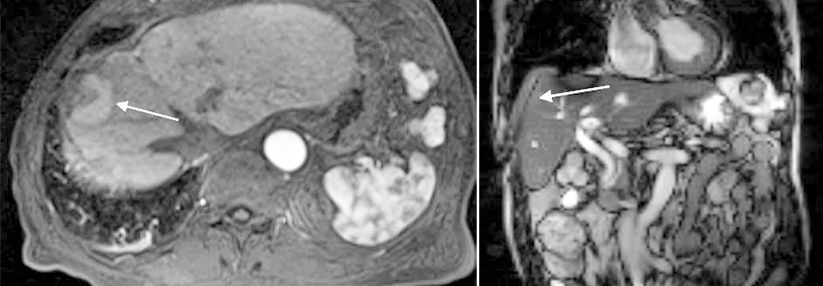

Forschende zielten mit der einarmigen multizentrischen Phase-2-Studie RACB darauf ab, die Wirksamkeit eines multidisziplinären Vorgehens mit Atezolizumab + Bevacizumab und anschließender chirurgischer Intervention beim initial nicht-resektablen hepatozellulären Karzinom (HCC) zu prüfen. Wie Dr. Maho Takayama, Universität Tokio, berichtete, war eine Inoperabilität definiert als intrahepatische vaskuläre Invasion und/oder synchrone extrahepatische Metastasen, metachrone extrahepatische Metastasen oder makroskopisch nachweisbarer Resttumor.